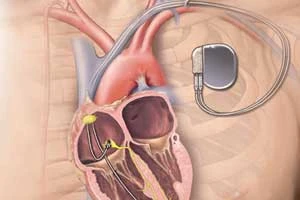

ICD (Implantable Cardioverter Defibrillator)

Advanced device to monitor and correct heart rhythm

Pacemaker Implantation

Device implantation to regulate abnormal heart rhythms

ICD (Implantable Cardioverter Defibrillator)

Advanced device to monitor and correct heart rhythm